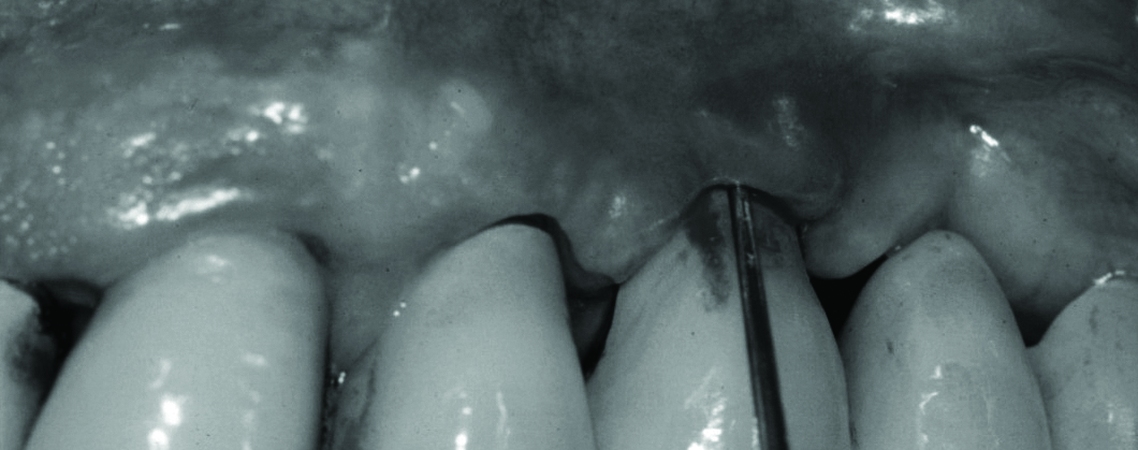

The number of osseointegrated implants is increasing and we all in daily practice encounter patients who have had them placed. Healthy peri-implant soft and hard tissues are essential for the stability and survival of dental implants. The role of the dental therapist, hygienist and clinician is paramount in ensuring that disease processes can be recognised early and dealt with accordingly. Patients are often unaware of the importance of regular peri-implant maintenance and the importance of this in early treatment of dental implant disease. The presentation will outline how to recognise healthy implant tissues and what clinical signs and symptoms indicate a disease process around the implants. It will look at the current protocol for when to treat and when to refer these patients as well as a protocol for use during the maintenance appointment.

• Recognising the differences between peri-implant and periodontal tissues.

• Recognising healthy peri-implant tissues and correct examination.

• Mucositis vs peri-implantitis.